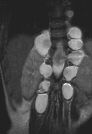

This 7 year old male presented to the cerebral palsy clinic with mild development delay, hyperactivity, and kyphosis. On physical examination he was slightly small for age (5th percentile weight for age, 10th percentile height for age) and had hyperactivity. He had no clonus or spasticity but a slightly clumsy gait. An MRI and plain x-rays were ordered (image 1, 2 & 3). After two years of brace wear the kyphosis increased to 78 degrees(image 4). The child is complaining of the brace and starting to refuse brace wear.

These mass appear to be meningoceles without neurofibroma.